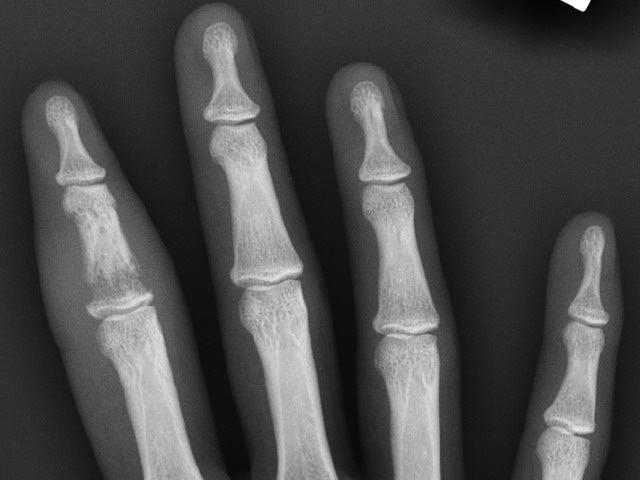

A geode is defined as a small hollow rock. The term microgeodic was coined by a French radiologist Maroteaux to describe the x-ray finding of very small (< 1mm) punched out lacunar-like osteolytic lesions (radiographic holes) in the small bones of the fingers of infants affected by this condition [1].

An x-ray of the affected digit shows small lucent spaces or 'microgeodes'. These are small osteolytic areas with a sclerotic lining. There may be a periosteal reaction.

The x-ray findings are localised to the affected phalanx (or phalanges when multiple digits are affected). In contrast, MRI has been reported to show bone marrow oedema in many phalanges of the affected hand, where clinical and radiological findings are absent [5,6].

X-ray